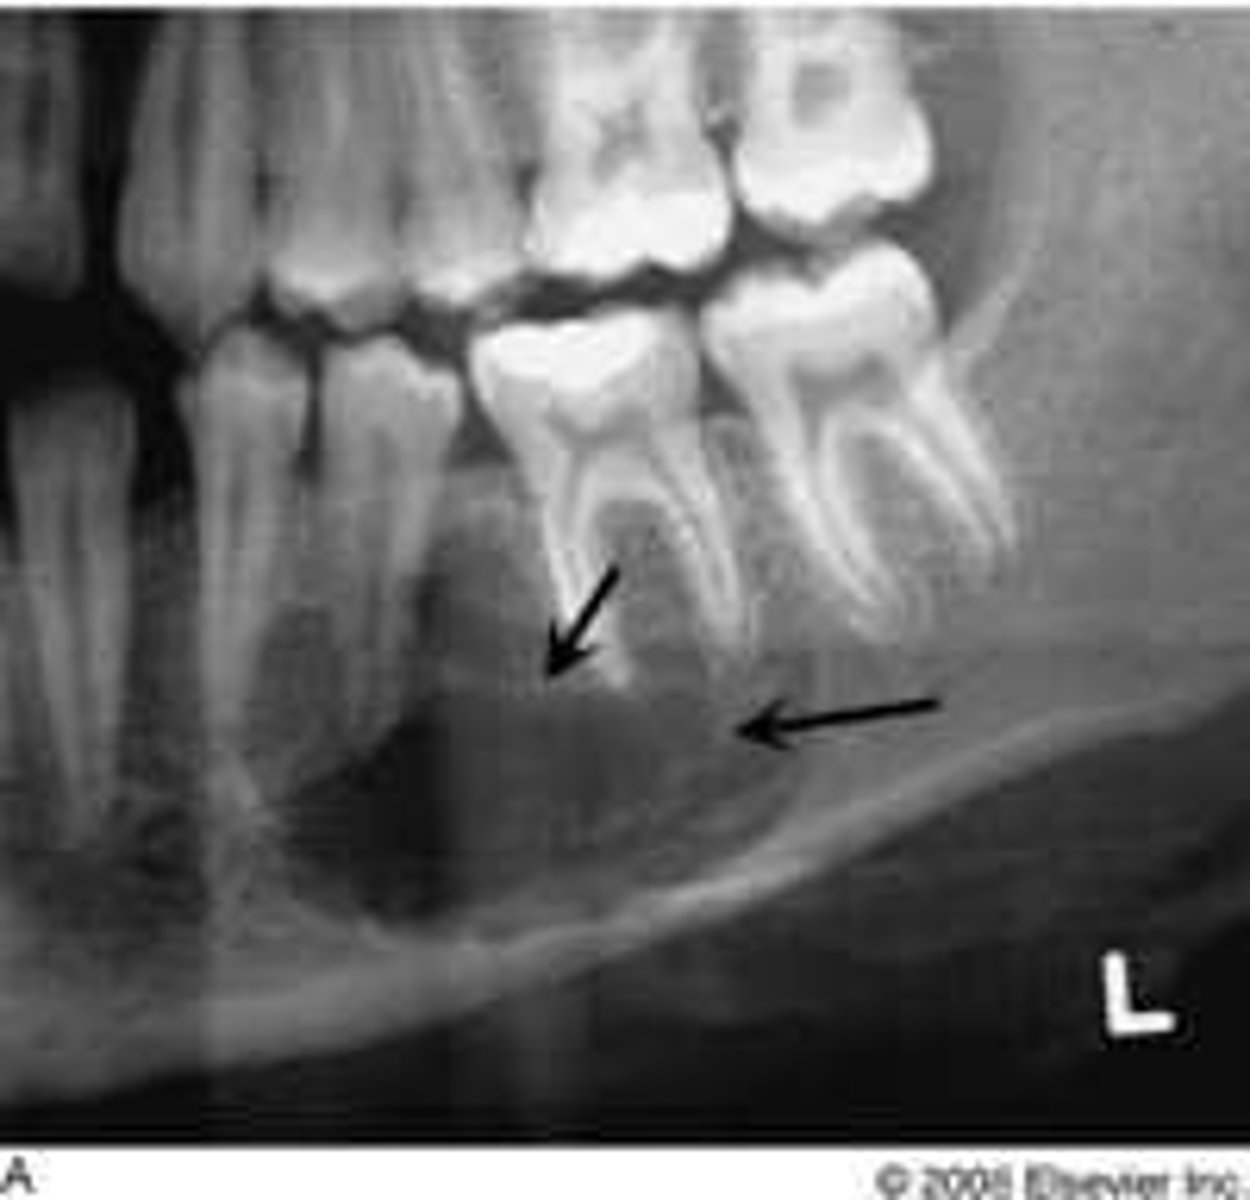

Central Giant Cell Granuloma

reactive lesion

multinucleated giant cells

Location of Central Giant Cell Granuloma

mandible

Periphery of Central Giant Cell Granuloma

well defined RL margin

Internal Structure of Central Giant Cell Granuloma

RL, granular pattern, wispy septae